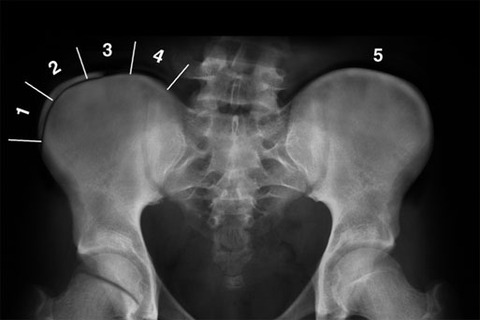

ちなみに、Risser signとは、骨盤の腸骨稜にみられる骨端核を用いた小児の骨の成長の評価方法のひとつです。骨端核が全く出現していない状態がgrade 0です。

上図のように上前腸骨棘から腸骨稜の1/4までがgrade 1、1/2までがgrade 2、、全域にわたり腸骨と癒合したらgrade 5で、骨の成長が停止したと判断され装具治療終了の指標となります。